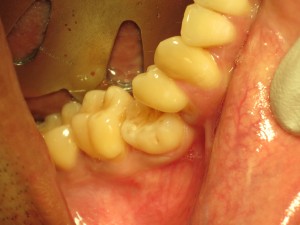

This is why it is so important to address your “stuck” baby teeth in a timely fashion. I have patients in their 30-40, still with their baby teeth, that come for possible replacement options. By then there is already extensive damage to the under lying bone and shifting of the adjacent. Hence they will need bone grafting & braces, to build up the bone and to also push the adjacent teeth into their original and optimal position. See the following case in a 34 year old patient still with his primary molars (Teeth #K & T):

Ankylosed #K Ankylosed #T